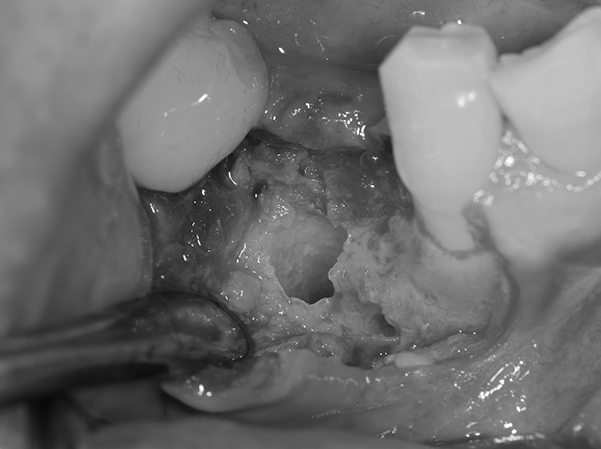

インプラント予定部位の骨の状態。 骨のてっぺんの部分は骨が薄く、また、横には大きな穴があいている状態。 これではインプラントを埋めてもしっかり入らずに、骨から飛び出してしまう。

麻布十番歯科のインプラント予定部位の骨の状態の症例写真

そのため、骨をてっぺんと穴の空いた部分に作る。 そのために、人工の骨をおき、チタンのメッシュで固定する。 この状態で6ヶ月ほど待機する。